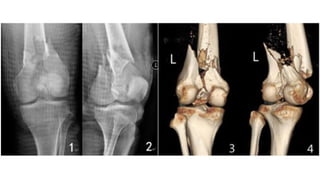

This document discusses femoral fractures, categorized by their location and severity, with classifications such as Garden classification. It outlines the types of fractures, including valgus impacted, non-displaced, partially displaced, and fully displaced, along with their surgical treatment options. Additionally, it briefly describes distal femur fractures, which occur just above the knee joint.